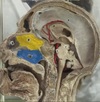

1. Name the structure?

2. What type of stimuli is the structure responsible for processing?

A

1. Pulvinar part of thalamus

2. Visual

2. What artery supplies this structure?

3. What is the specific embryonic origin of this structure?

4. What substances are produced by this structure?

5. What is the function of this structure?

1. Pineal Gland/ body

2. Posterior Cerebral artery

3. Neural ectoderm; root of Diencephalon

4. Melatonin and Serotonin

5. Maintains circadian rhythms

Melatonin controls sleep wake function of body